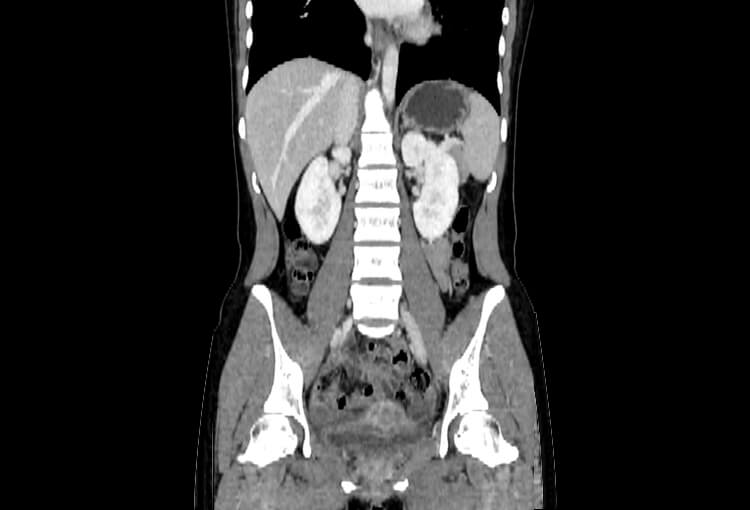

Before and After Denoising

120 kV / 20 mAs / 1 mm

Before FBP (Noise 189) VS After ClariCT.AI (Noise 46) 76% Denoising